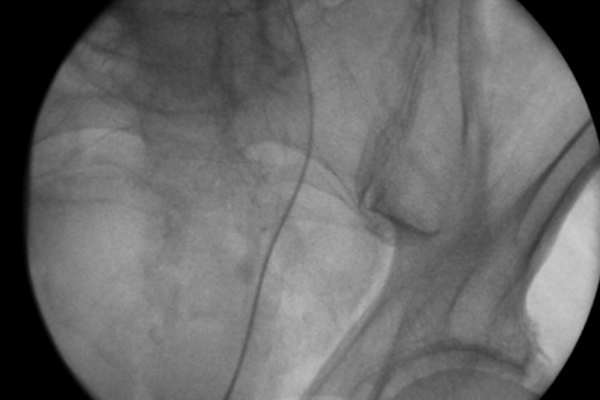

Meeting in the middle: a review of the rendezvous technique to treat impassable ureteric strictures and transected ureters